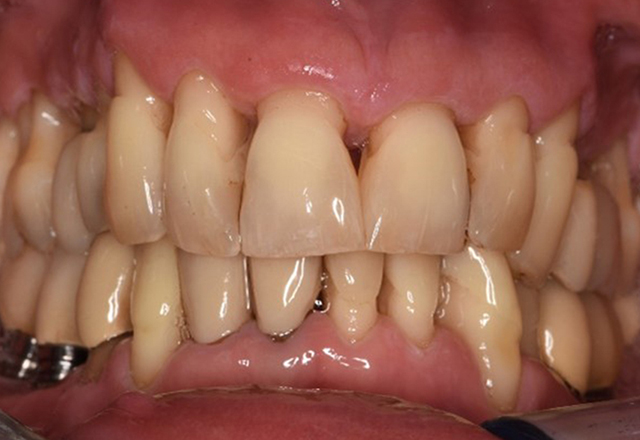

The healthy patient with pre-existing periodontal disease & peri-implantitis

A 52-year-old patient presents at a preventive care session. The patient has no systemic disease and is not taking any medication. He has had various dental treatments and also has two active carious lesions. In addition, the patient has four implants (2nd, 3rd and 4th quadrants). He is revealed to have early periodontal disease (stage IV, grade B). His periodontal condition is stable; a probing depth of Probing depths (ST) of 5 mm is only evident at the implant in region 36. Gingivitis is also identified. more

The healthy patient with early periodontal disease

The 68-year-old patient has no general health conditions and is not taking any medication that may be relevant to her oral health, and her lifestyle does not pose any particular risk. The patient has two dental implants (3rd quadrant, for five years) and a previous case of periodontal disease (stage IV, grade B periodontitis) with tooth loss. Currently the periodontal conditions are stable. However, periodontitis significantly increases the biological complications of implantations and there is a risk of implant loss (21). Four recommendations can be determined for the prophylaxis session. more